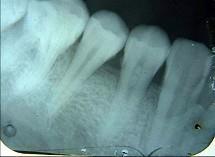

问题 以下哪一项是诊断牙髓钙化的主要手段 ( )

选项 A.电活力测验 B.视诊 C.X线片检查 D.温度测验 E.光纤透照

答案 C